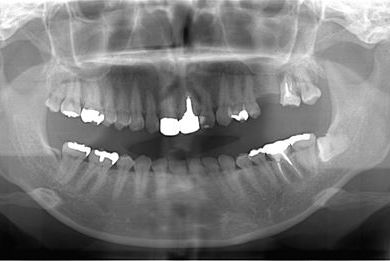

| 性別/年齢 | 女性 / 30歳 | ||||||||||||||||||||||||||||||||

| 主訴 | 上の奥歯を抜歯すべきかどうか、抜歯する場合はインプラント治療が可能かどうかの相談。 | ||||||||||||||||||||||||||||||||

| 治療方針 | ソケットリフトにて上顎洞を拳上し、インプラント治療を可能にする。 | ||||||||||||||||||||||||||||||||

| 治療内容 | インプラント2本(ソケットリフト)、メタルボンドセラミッククラウン1本 | ||||||||||||||||||||||||||||||||